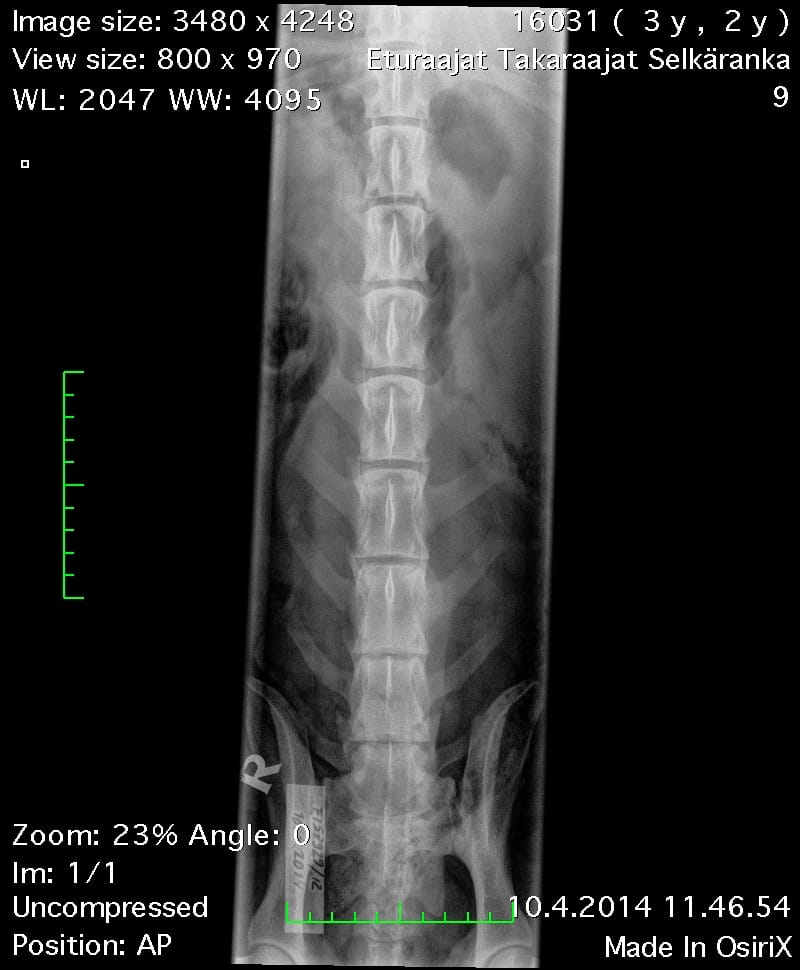

| Hips: | A/A | |

| Spine: | SP0, LTV4 (8 lumbosacral vertebrae) | |